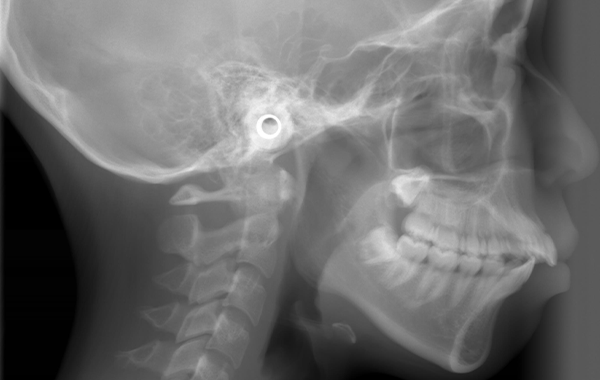

| 治療 内容 | 出っ歯感が強かったため、上の歯を2本抜歯し、抜歯したスペースを有効に使うため、インプラントアンカーを埋入して治療を行いました。 出っ歯感や口元の突出感を本人はとても気にされていたので、治療後、治療期間の短かさと口元の変化にご家族の方からも喜んでいただけました。 |

口元が出ているのが気になると矯正治療を希望されました。 口元の突出感を治したい要望が強かったため、4本小臼歯を抜歯し、 その抜いた隙間を突出感改善に 無駄なく使うため、 インプラントアンカー を上顎に2本埋入し治療を行いました。口元の突出感が大きく改善し、すっきりとした素敵な口元になりました。 |

| 治療 内容 | 出っ歯が主訴で矯正をすることになりました。 昼間1時間と就寝時のEF line(マウスピース)で、既に5か月後には出っ歯感が解消しました。写真は9か月後の写真です。 本人がきちんと指示通りに使ってくれれば治りも早く、キレイになるのも早いです。 Ⅰ期治療でここまで治しておけば、Ⅱ期治療(すべての永久歯を並べる治療)で永久歯を抜かずに治せるようになるので、歯の土台作りをするⅠ期治療は大切だし、やっておいて正解ですね。しかも、II期治療の治療がスムーズになるので、治療期間が短くなります!(通常2年かかるところ1年以内に終わることもあります。) 横顔も下顎が引けている感じの出っ歯感がありましたが、治療後は上下のあごのバランスがよくなり、キレイな横顔になりました。 |